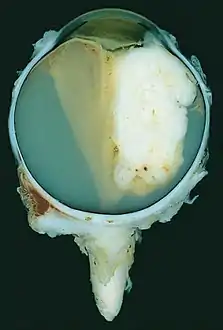

![]() | |

| A pathology specimen of a retinoblastoma tumor from an enucleated eye of a 3-year-old female | |

Gross and microscopic appearances of retinoblastoma are identical in both hereditary and sporadic types. Macroscopically, viable tumor cells are found near blood vessels, while zones of necrosis are found in relatively avascular areas. Microscopically, both undifferentiated and differentiated elements may be present. Undifferentiated elements appear as collections of small, round cells with hyperchromatic nuclei; differentiated elements include Flexner-Wintersteiner rosettes, Homer Wright rosettes,[29] and fleurettes from photoreceptor differentiation.[30]